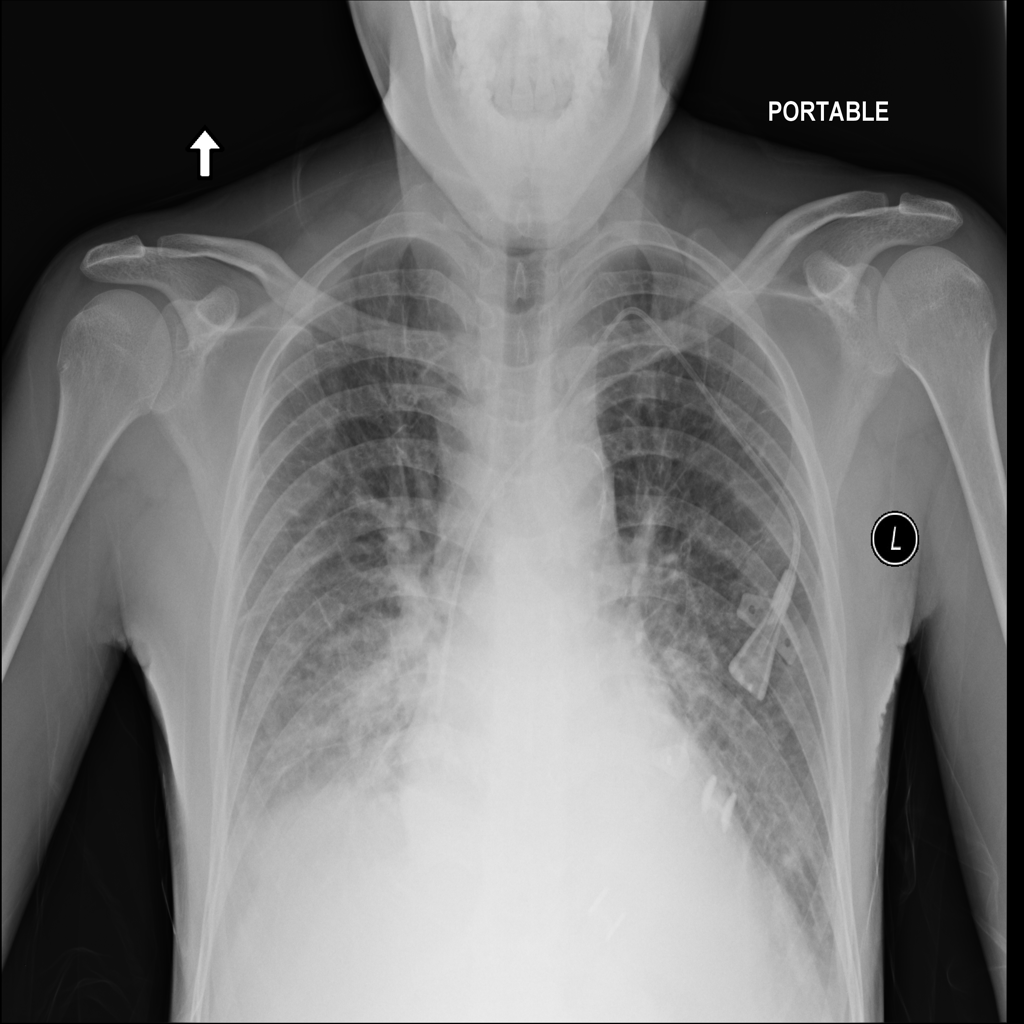

PAT-24D9 · IMG-006Edema

PAT-24D9 · IMG-006

AP